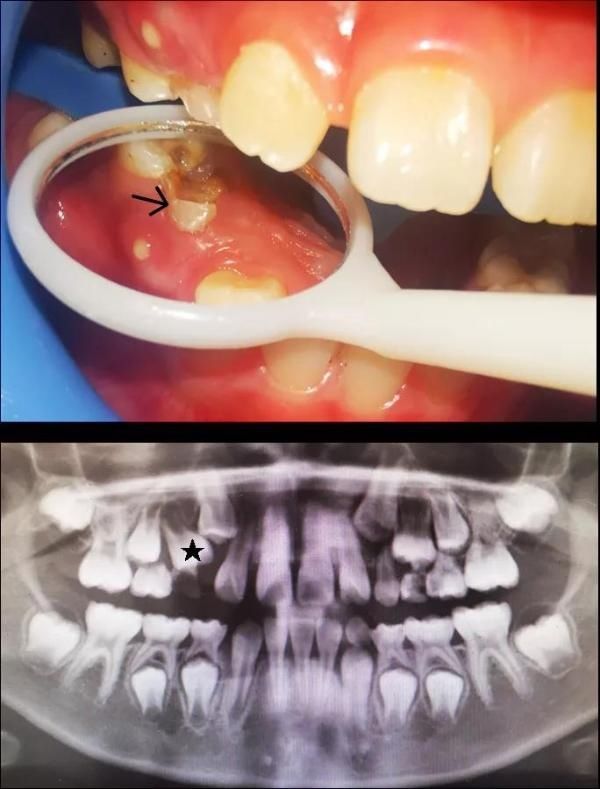

【6岁孩子长出双排牙,都怪家长“太勤快”?这种方式,爸妈们要改改……】经过检查,王医师确认,小元宝整齐的下前牙内侧确实冒出了两颗“不速之客”,而这正是将来要接替前面两颗乳牙的恒牙。

若恒牙已经萌出了,但相对应的乳牙却没能脱落,就会一起并排留在口腔中,就导致了“双排牙”,专业上称为“乳牙滞留”。

王医生回忆,之前门诊来过一位7岁的小朋友,右上排一个乳牙牙冠已经完全蛀掉。询问家长得知,来就诊的之前几个月,小朋友就已经因为这颗牙齿感染发烧过两次,烧退后也一直未处理该牙。

后来因为发现这颗牙齿旁边疑似有新牙长出,才来医院就诊。医生检查发现,孩子的这部分牙龈已经有脓液溢出了,而影像学检查提示上方正在萌出的恒牙牙根才刚刚开始发育——这样的双排牙很可能一个也保不住。